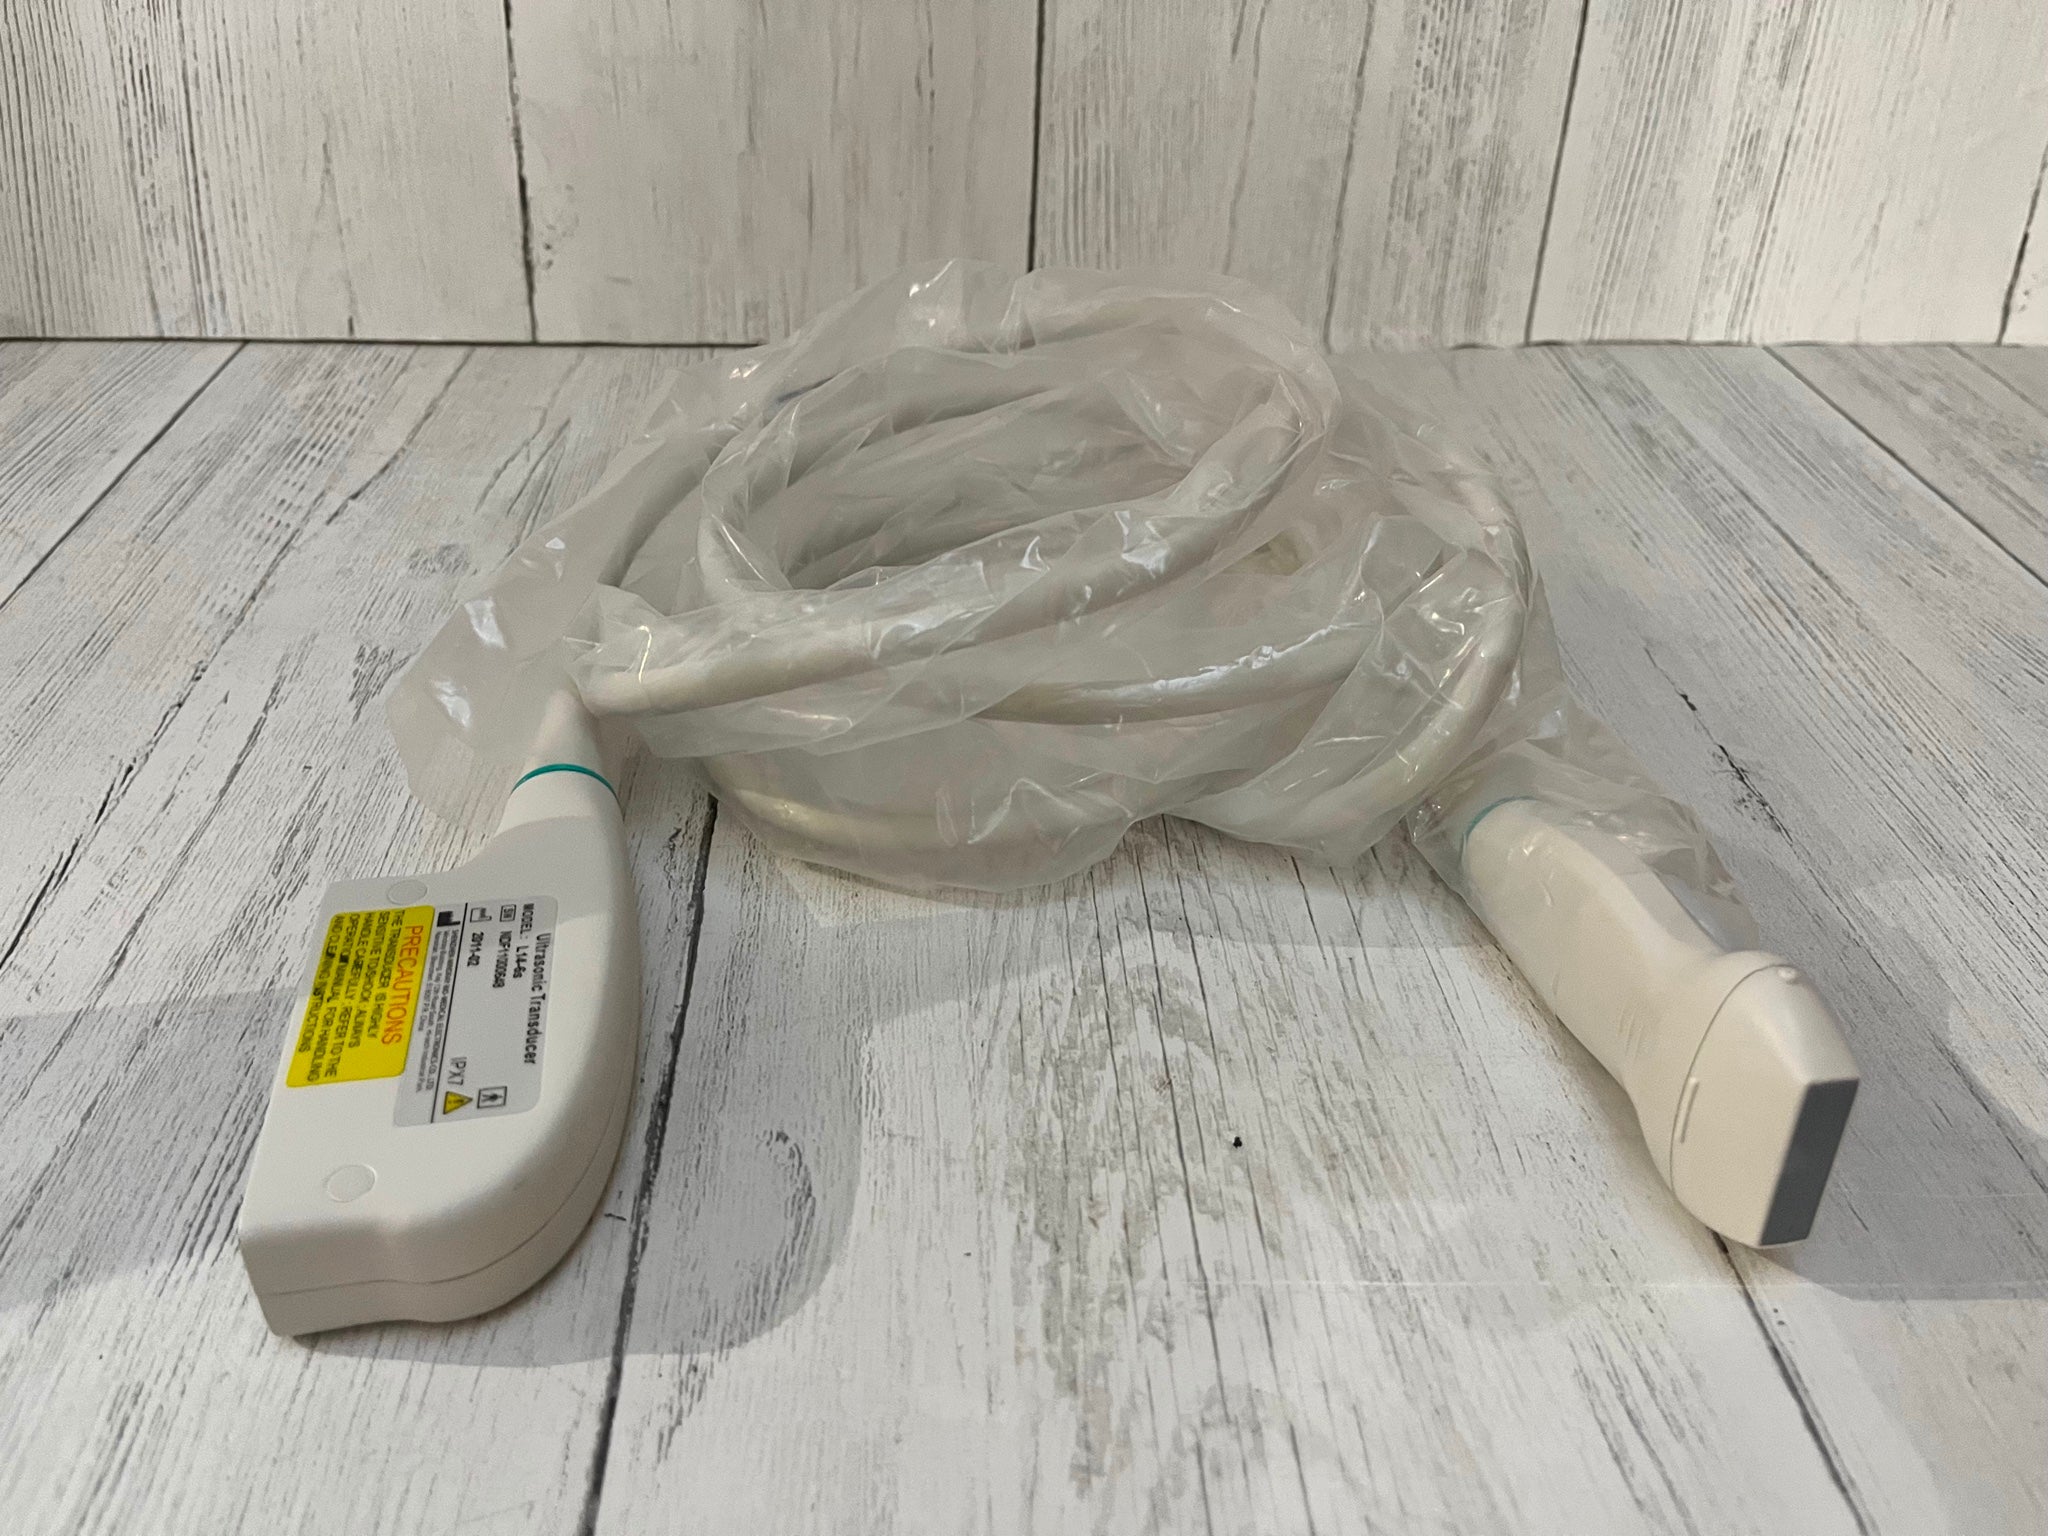

2017 GE ML6-15 -RS for GE S8 ,S6 Ultrasound

Sale price$ 7,675.18